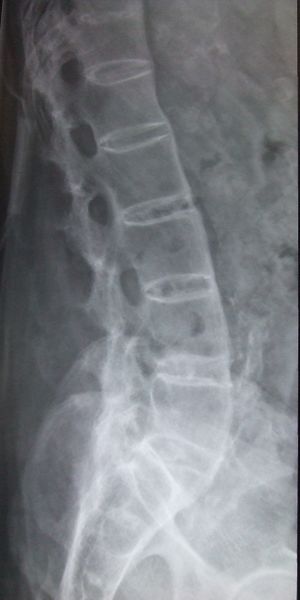

يبدأ التهاب الفقار المقسط في صغار البالغين بألم مبهم في أسفل الظهر، ويبوسة مديدة تالية للراحة تتحسن جزئياً بالحركة والتمارين الرياضية. ينتشر الألم إلى الاليتين والقسم الخلقي من الساقين. كما يحدث ألم في القفص الصدري بإصابة المفاصل الغضروفية المركزية فيه، وقد يكون لهذا الألم صفات جنبية، ويظهر الألم أيضاً في مفاصل قبضة القص Manubriosternal والمفاصل القصية الترقوية. إن التهاب ارتكازات الأربطة والأوتار عرض بارز وقد يكون العرض الأول. وينجم الألم عن التهاب الأصابع Dactylitis ' أو وتر أشيل، أو اللفافة الأخمصية، أو عرف الحرقفة iac أ I Crest. تكون الإصابة المفصلية بشكل الام مفصلية، أو التهاب مفاصل عديد، يصيب المفاصل الزليلة الدانية وبشكل غير متناظر كالكتفين والمرفقين والركبتين ونادرا المفاصل الصغيرة القاصية. وتترافق هذه الإصابة بيبوسة صباحية مديدة وأحياناً بتورم الا أنه من غير الشائع حدوث إصابة مفصلية تاكلية شديدة.

يحدث التهاب العنبية الأمامي في حوالي ربع المرضى، ويتظاهر بألم واحمرار وخوف من الضياء، وتكون هذه الإصابة نوبية، وحيدة أو ثنائية الجانب. يبدي الفحص السريري نقصاً في حركية العمود الفقري، مع فقد تام أو جزئي للقعس القطني الفيزبولوجي، وزيادة في الحدب الظهري. أما المظاهر المتأخرة فتشمل تحدد حركة جدار الصدر في الشهيق العميق (أقل من 2.5 سم) مع انحناء تدريجي، وثبات العمود الفقري والرأس في وضعية العطف. ويمشى المريض جاراً قدميه Shuffling Gait مع تفاوت شدة إصابة المفاصل المحيطة.[2]